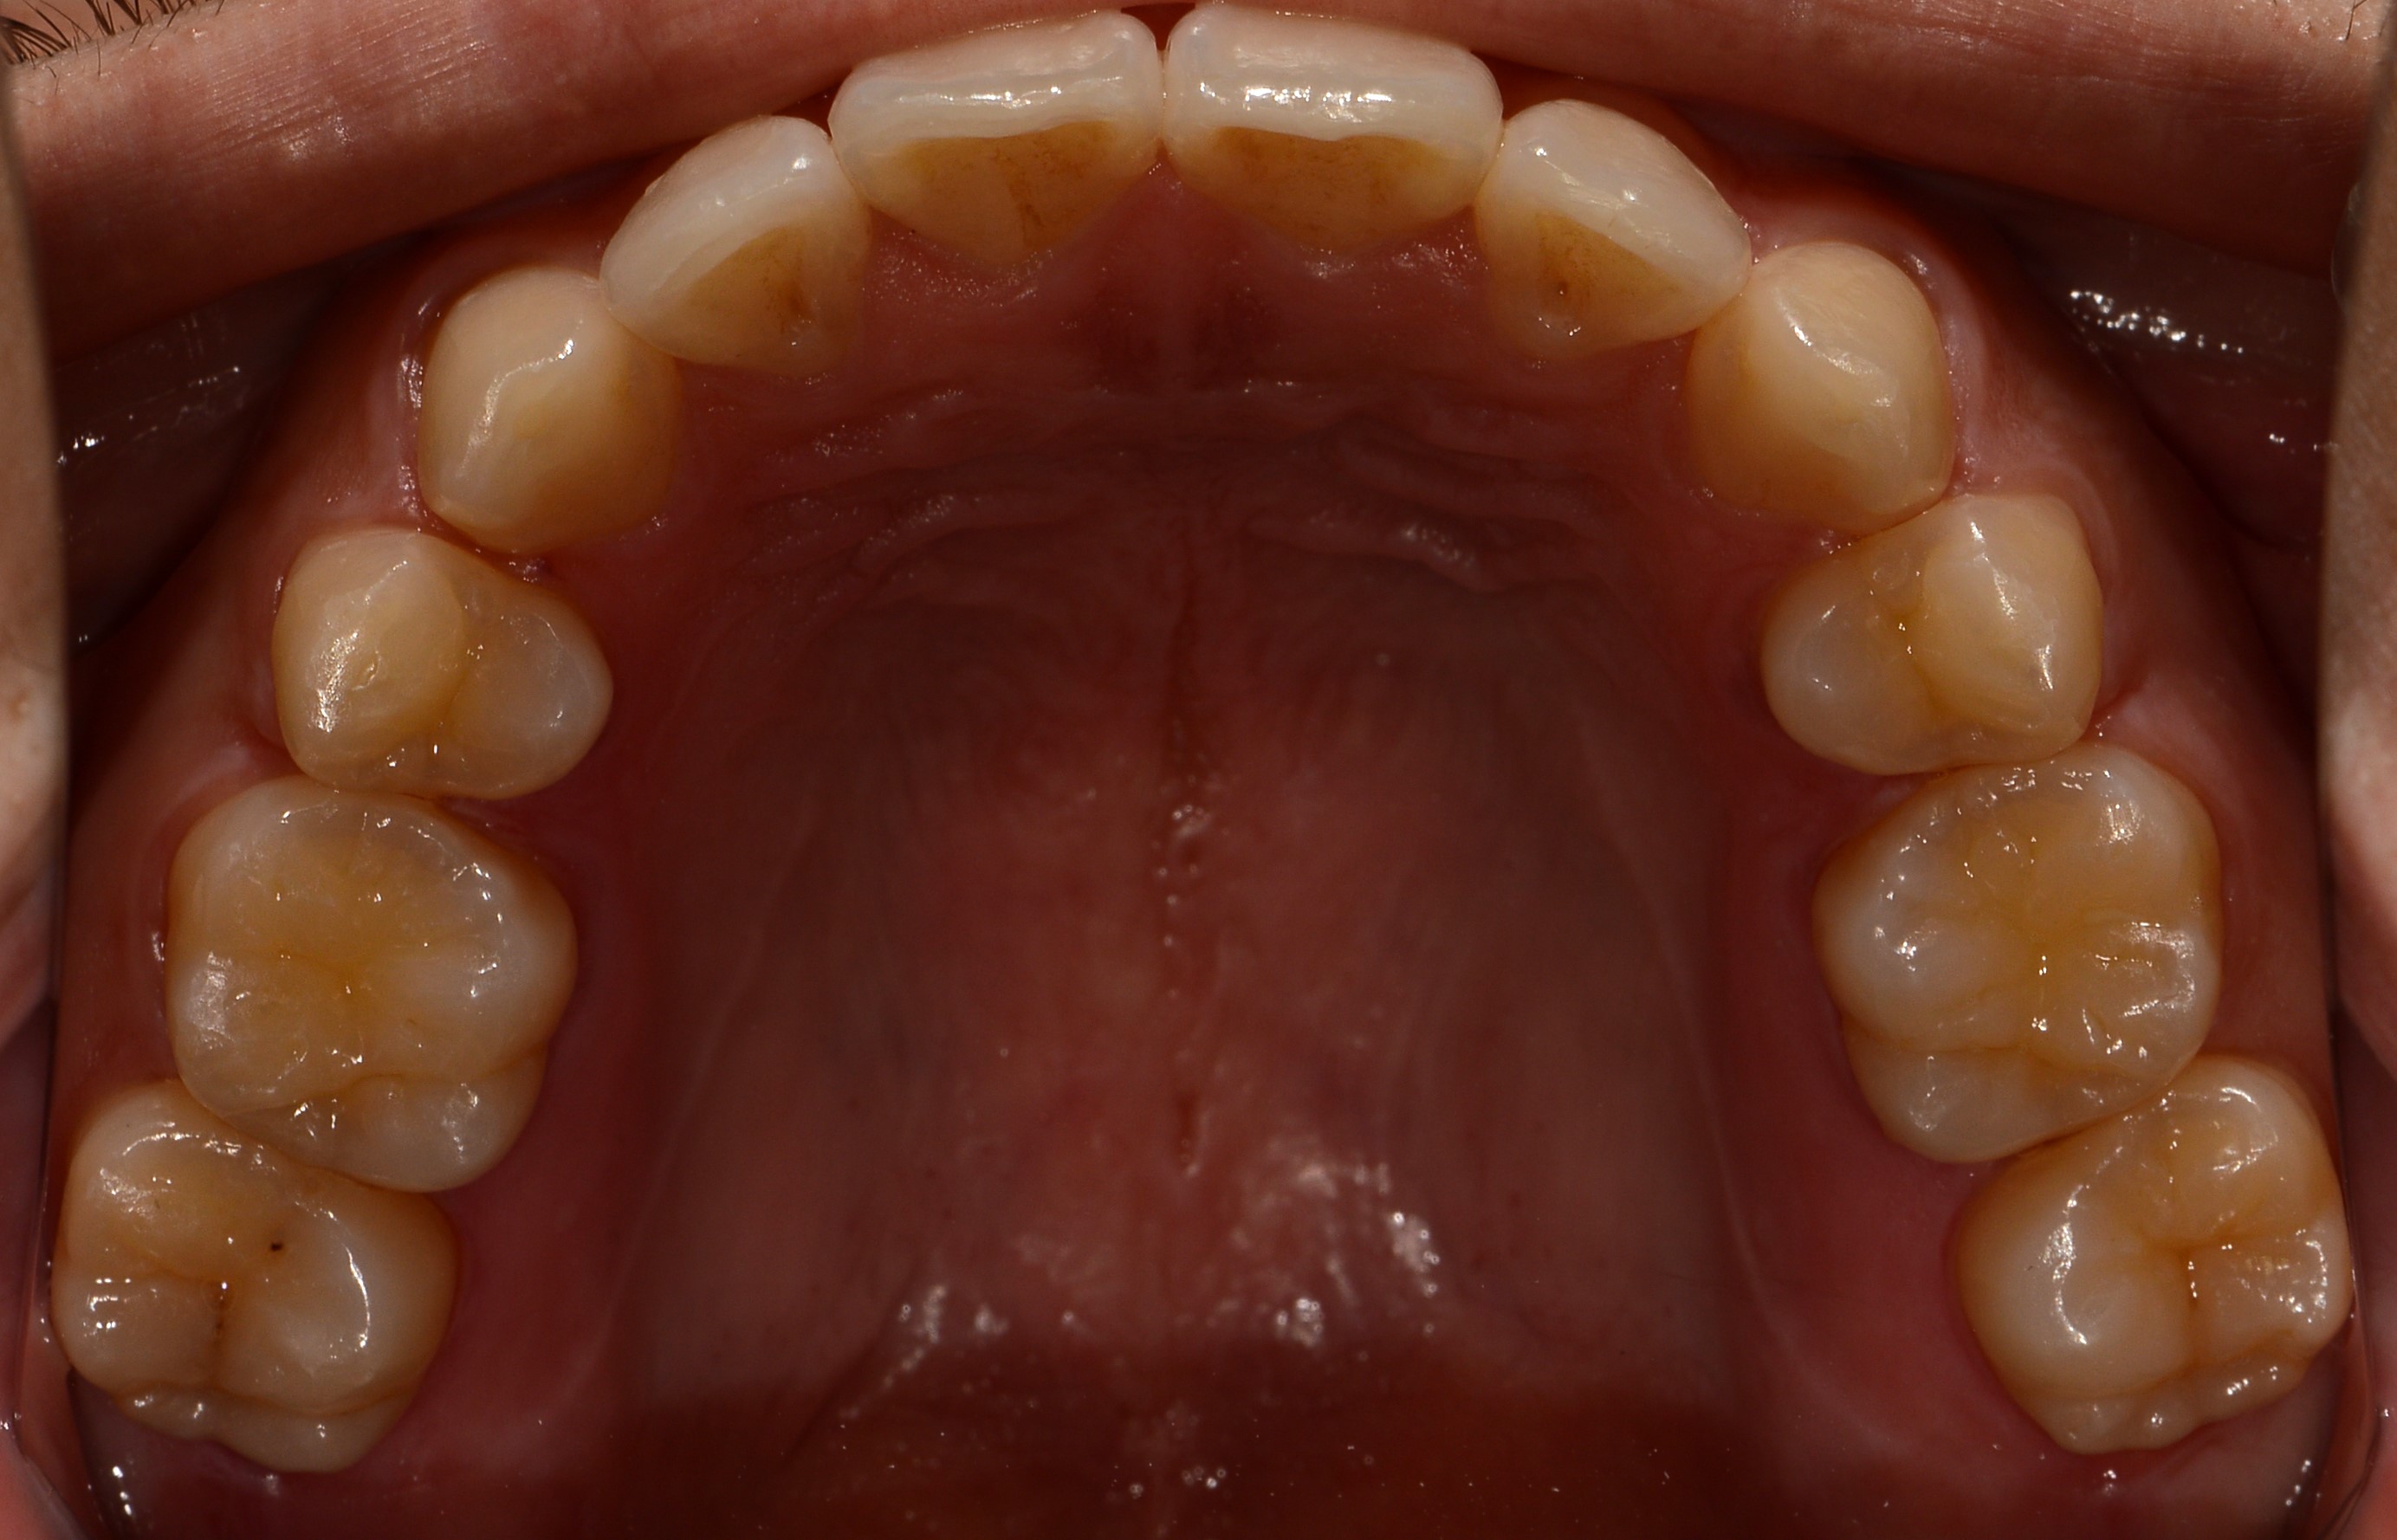

치료 후 사진입니다.